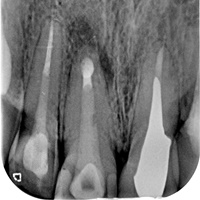

Pacjent z rozległa torbielą 21, 22. Po przygotowaniu endodontycznym wykonano zabieg resekcji. Na uwagę zasługuje delikatne wykonanie zabiegu - na błonie śluzowej i dziąsłach nie sa widoczne blizny pozabiegowe, co jest bardzo ważne u pacjenta z wysoka linią uśmiechu.